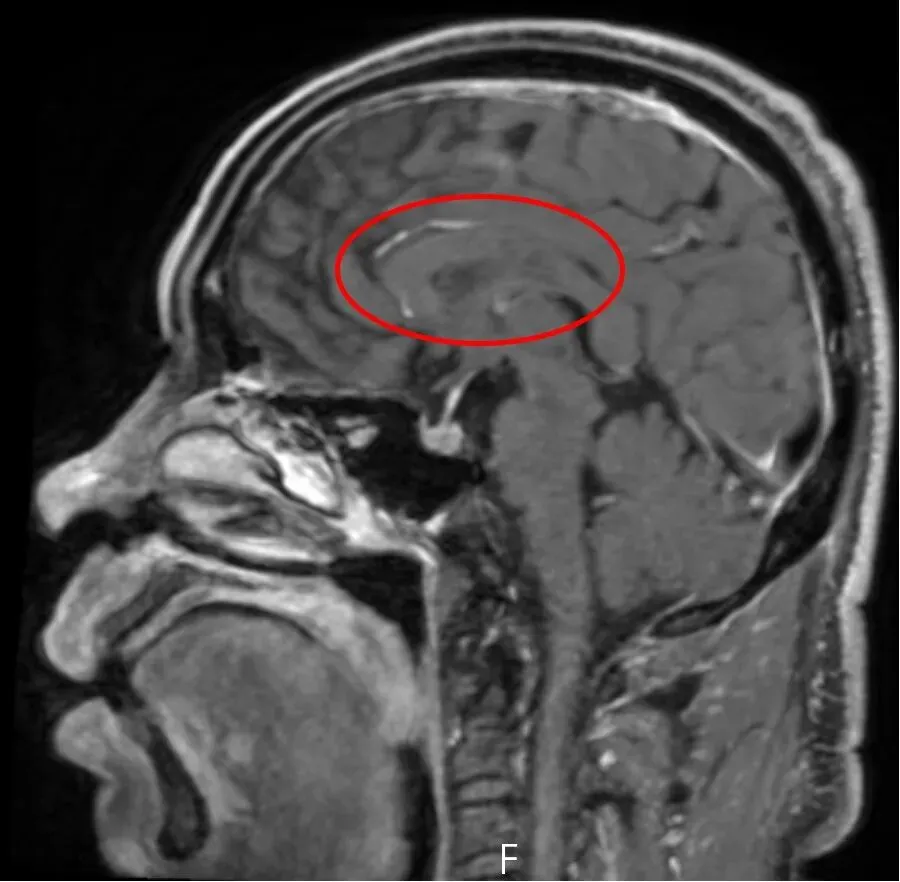

近日,一名58岁的男性患者因“双膝关节麻木”入住我院脑病科一病区,初诊怀疑腰椎问题,次日出现感觉异常,经磁共振(MRI)检查,结果显示他患有双侧额顶叶多发新鲜脑梗死,经抗血小板、强化降脂等常规治疗后好转,但短短3天后,患者症状便再次发作,复查磁共振显示,患者又出现多处新发脑梗死,且症状较上次更明显。面对常规治疗无效的困境,脑病科一病区医疗团队迅速调整思路,通过血栓基因检测,发现患者对他汀类药物反应特殊,随即调整降脂方案。更关键的是,患者双侧大脑半球的多发脑梗死发生在不同的时间段,不同部位,这使得病因的进一步明确成为治疗的关键。

患者第一次就诊,双侧大脑半球多发脑梗死